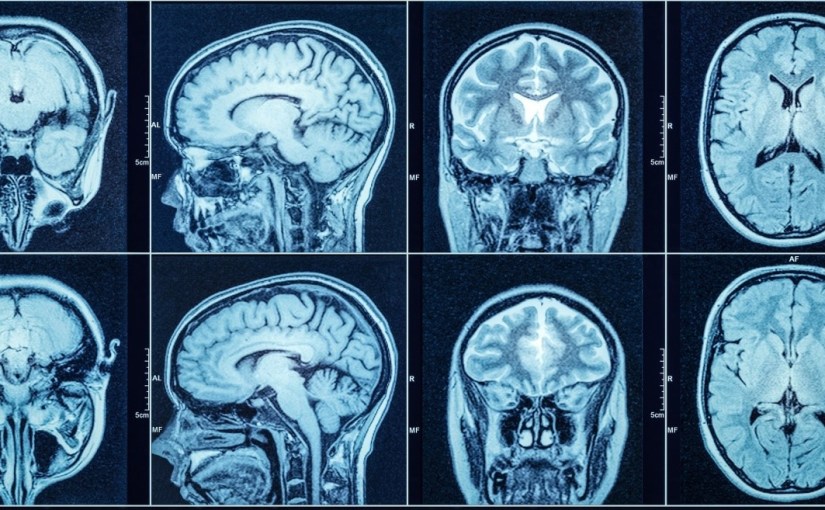

Magnetic Resonance Imaging (MRI)

Magnetic resonance imaging (MRI) is a second type of imaging study doctors might order when they suspect a TBI. This scan uses powerful magnets combined with radio waves to generate a detailed picture of the brain. An MRI might be ordered if the patient’s symptoms don’t improve after the injury or once their condition has stabilized. It helps doctors to understand the extent and severity of the damage resulting from a TBI. Standard MRIs don’t allow doctors to see the microscopic damage involved in a concussion or mild TBI. However, newer, specialized MRIs do allow doctors to evaluate structural and functional changes in the brain to aid them in diagnosing mild TBIs.